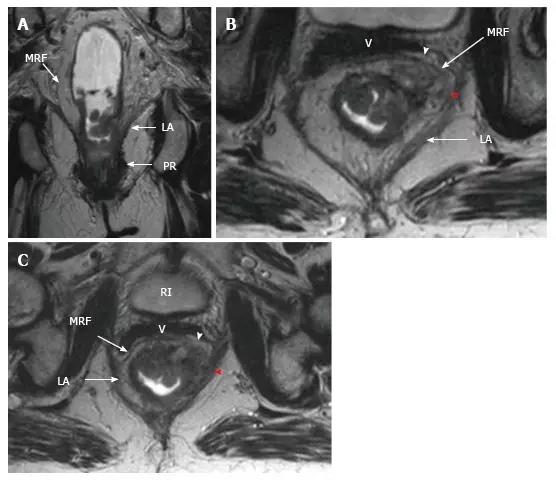

2.直肠系膜筋膜距离

如果在 CRT 后距离 MRF 至少 1 毫米观察无肿瘤边缘则认为 CRM 未累及,阴性预测值达 98%,但阳性预测值很低。有些直肠癌,CRT 导致肿瘤容积明显减少同时,也导致最初与 MRF 相接的缘收缩,此时难以确定此区域是否存在肿瘤细胞(图 22 和 图 23)。

图 23. 放化疗对直肠肿瘤和周围切缘的影响。不同病人的 T2 加权轴位磁共振图像(上:基线,下:CRT 后)。A. 在没有 MRF 侵袭的 ypT2 直肠肿瘤中,在直肠系膜筋膜(箭头)处厚厚的低信号组织浸润导致过度分期;B. 在没有 MRF 侵袭的 ypT3 直肠肿瘤中,肿瘤的纤维性纤维性缩小,CRM 阳性可疑(箭头);C. 直肠肿块明显缩小,低信号强度浸润直肠系膜筋膜(箭头)。手术中证实肿瘤侵犯了直肠系膜筋膜。